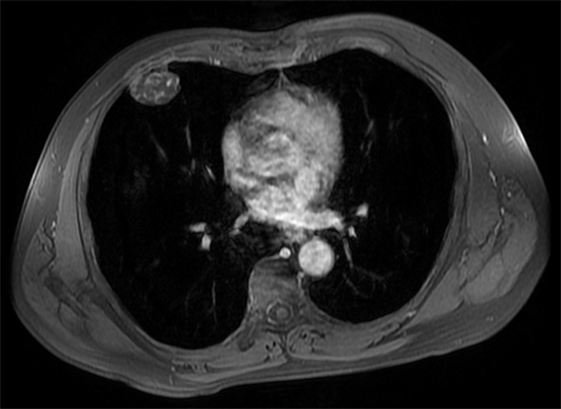

A 60-year-old Hispanic male presented to his primary care physician office with an asymptomatic, but palpable right anterior chest wall mass. The patient has no significant past medical history except for a clavicular fracture sustained during soccer. Physical examination revealed an asymptomatic 4 cm soft tissue palpable mass of the right anterior chest wall. The skin was intact, no erosive markings were present. The patient’s laboratory work up was unremarkable. Radiology work up included CT chest, MRI of the chest and PET/CT. His CT chest axial series on bone windows demonstrated a 2.8 × 3.8 × 2.9 cm pleural based soft tissue mass eroding through the right anterior fifth rib (Figure 1). There was mild compression of the nearby lung parenchyma, however no pulmonary lesions were identified. Further characterization of the mass by MRI contrast enhanced images of the chest revealed a well-circumscribed pleural based T1 hypo-intense avidly enhancing soft tissue mass in the right anterior chest wall involving the right anterior fifth rib and into the overlying sub-pectoral soft tissues (Figure 2). The mass also demonstrated restricted diffusion which is indicative of high cellularity (Figure 3 and Figure 4). PET/CT imaging revealed mild hypermetabolic activity of the mass with maximum SUV of 1.9 (Figure 5).

Figure 2. Axial post-contrast T1 weighted MRI image is noted for avid enhancement of the destructive anterior chest wall mass.